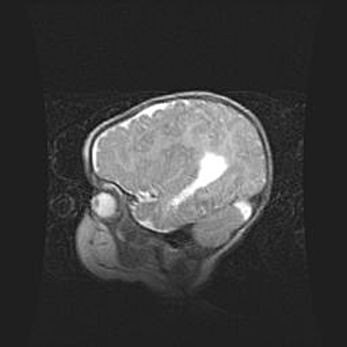

Сообщающаяся гидроцефалия. Кистозная энцефаломаляция головного мозга.

Возраст: 3 месяца 4 дня

Вес: 3100 г

Пол: женский

Окружность головы: 34 см

Срок гестации: 31 неделя

Кистозная энцефаломаляция головного мозга - одна из форм поражения головного мозга в детском возрасте. Характеризуется возникновением множественных и распространённых кист в коре, белом веществе и подкорковых образованиях головного мозга у плодов, новорождённых и детей раннего возраста. Развитие кистозной энцефаломаляции связано с внутриутробной асфиксией и гипотонией, родовой травмой, тромбозом синусов, пороками развития сосудов, инфекциями, сепсисом и другими причинами. Наиболее значимые инфекционные агенты: вирусы простого герпеса, цитомегалии, краснухи, токсоплазмы, энтеробактерии, золотистый стафилококк и другие.